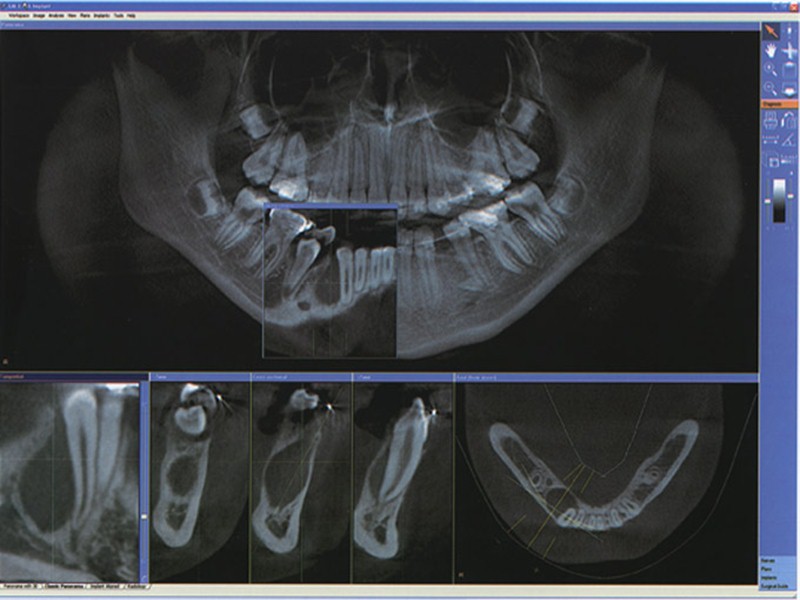

Объективно: в ранних стадиях отмечается веретенообразное вздутие тела челюсти; при этом опухоль представляется гладкой или слегка неровной – бугристой, плотной (костной) консистенции. Кожные покровы над опухолью в цвете не изменены, собираются в складку; иногда несколько бледноваты. Позднее появляются признаки кистозного новообразования: очаги пергаментного хруста, флюктуация; кожа над опухолью истончается, бледнеет, появляется видимая сосудистая сеть, она трудно собирается в складку. Со временем кожа истончается и даже может доходить до изъязвления над местами наиболее выраженных костных выпячиваний. Регионарные лимфоузлы не увеличены при том условии, если содержимое кистозных полостей еще не нагноилось и к опухолевому процессу не присоединилось воспаление кости. Зубы в области опухоли обычно достаточно устойчивы, но могут быть и несколько расшатаны (при наличии хронического воспалительного фона). Слизистая оболочка десны нормальной окраски или цианотична. Рентгенографические данные разнообразны. Важнейшей рентгенологической чертой адамантином является различная степень прозрачности полостей. Для гистологического строения адамантином характерно отсутствие четких границ опухоли, наличие отростков и выступов, инфильтрирующих окружающие ткани. Этим определяется необходимость радикального удаления опухоли, отступая от рентгенографически определяемых ее очертаний.

Одонтома мягкая (амелобластическая фиброма), клинически по своему течению напоминает амелобластому. Однако наблюдается чаще в период формирования зубов. По мере роста опухоли кость вздувается, а затем разрушается кортикальная пластинка челюсти, и опухоль прорастает в мягкие ткани. Выбухающая опухолевая ткань имеет темный цвет. Опухоль эластичная, кровоточит и может изъязвляться. Зубы подвижны и смещены. Гистологически определяются эпителиальные разрастания и нежноволокнистая соединительная ткань в виде тяжей. В опухоли иногда располагается не полностью сформированный постоянный зуб. Течение опухоли обычно доброкачественное, однако в ряде случаев выявляются признаки инфильтративного роста (прорастание в мягкие ткани, изъязвление). Рентгенологическая картина опухоли напоминает амелобластому: истончение коркового вещества, несколько кистоподобных участков просветления. В костных полостях могут быть зубы и зачатки зубов. Границы опухоли четкие. Лечение мягкой одонтомы хирургическое - резекция челюсти в пределах здоровых тканей для профилактики ее рецидива. Выскабливание опухоли до здоровой кости может вести к рецидивированию и даже малигнизации.